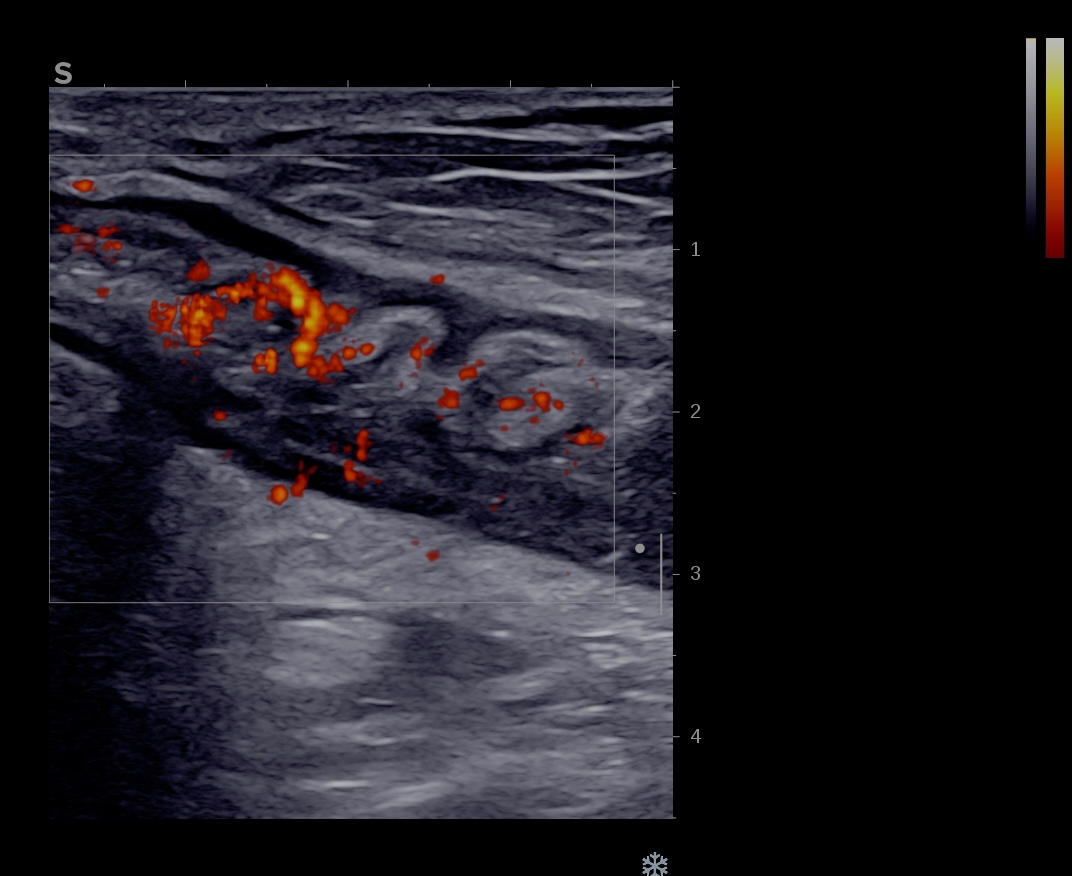

- Limberg 3 signal abondant dans la paroi et la graisse mésentèrique vascularisation marquée (= Inflammation sévère)

Activité Doppler intense de la paroi et de la graisse

Maladie de Crohn intense activité Doppler paroi et graisse

Il exite différents doppler qui peuvent tous être utilisés pour mesurer l'activité inflammatoire de la paroi intestinale.

- Le Doppler Couleur (qui enregistre la direction des flux (rouge se rapproche de la sonde et bleu s'éloigne de la sonde)

- Le Doppler Energie (qui ne mesure que les flux d'une seule couleur)

- La microcirculation (fournie par certains constructeurs)